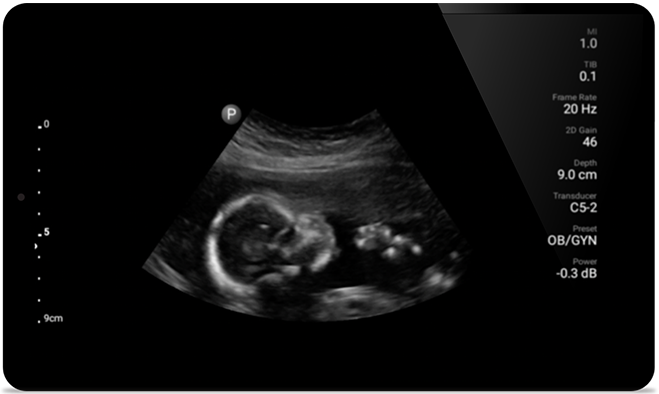

• 5 to 2 MHz extended operating frequency range • 50mm radius of curvature • 2D, color Doppler, M-mode, advanced XRES and multivariate harmonic imaging, SonoCT • High-resolution imaging for deeper applications: abdominal, gall bladder, OB/GYN and lung imaging preset optimizations • Center line marker • USB-C transducer with replaceable cable